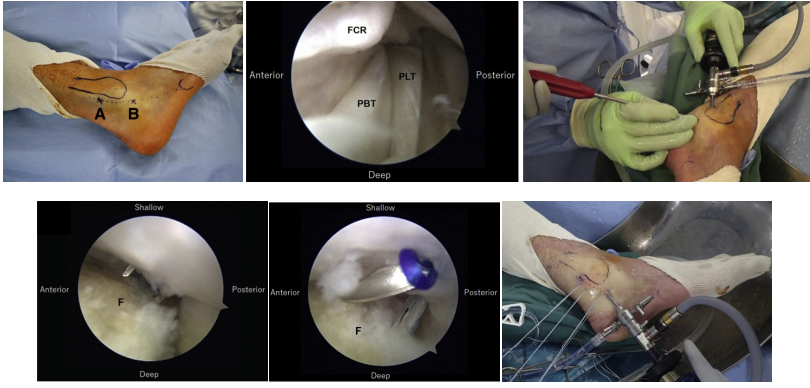

SPR撕脱关节镜手术锚钉修复

内镜下腓骨沟加深手术

大部分急性损伤可以使用直接缝合修复,对慢性损伤则需根据患者的具体病理改变选择,如单纯的支持带结构损伤,可以直接缝合修复。如果直接修复不够稳定,需用其他组织加强。如果腓骨外踝窝较浅时,就需要使用加深手术。